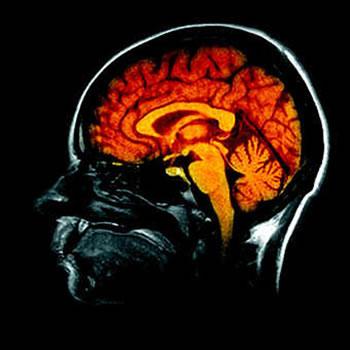

La neuropsychologie, une science très complexe

Concernant la R & D dans le processus d'innovation, pour la première fois en Algérie, une formation en imagerie cérébrale a eu lieu dans le cadre du magistère mort-né. Toutefois, l'unique promotion que j'ai pu en sauver et mes doctorants, notamment les médecins et les étudiants du Master, en bénéficient, en prévision de l'acquisition, par le laboratoire, de la technologie y attenant.